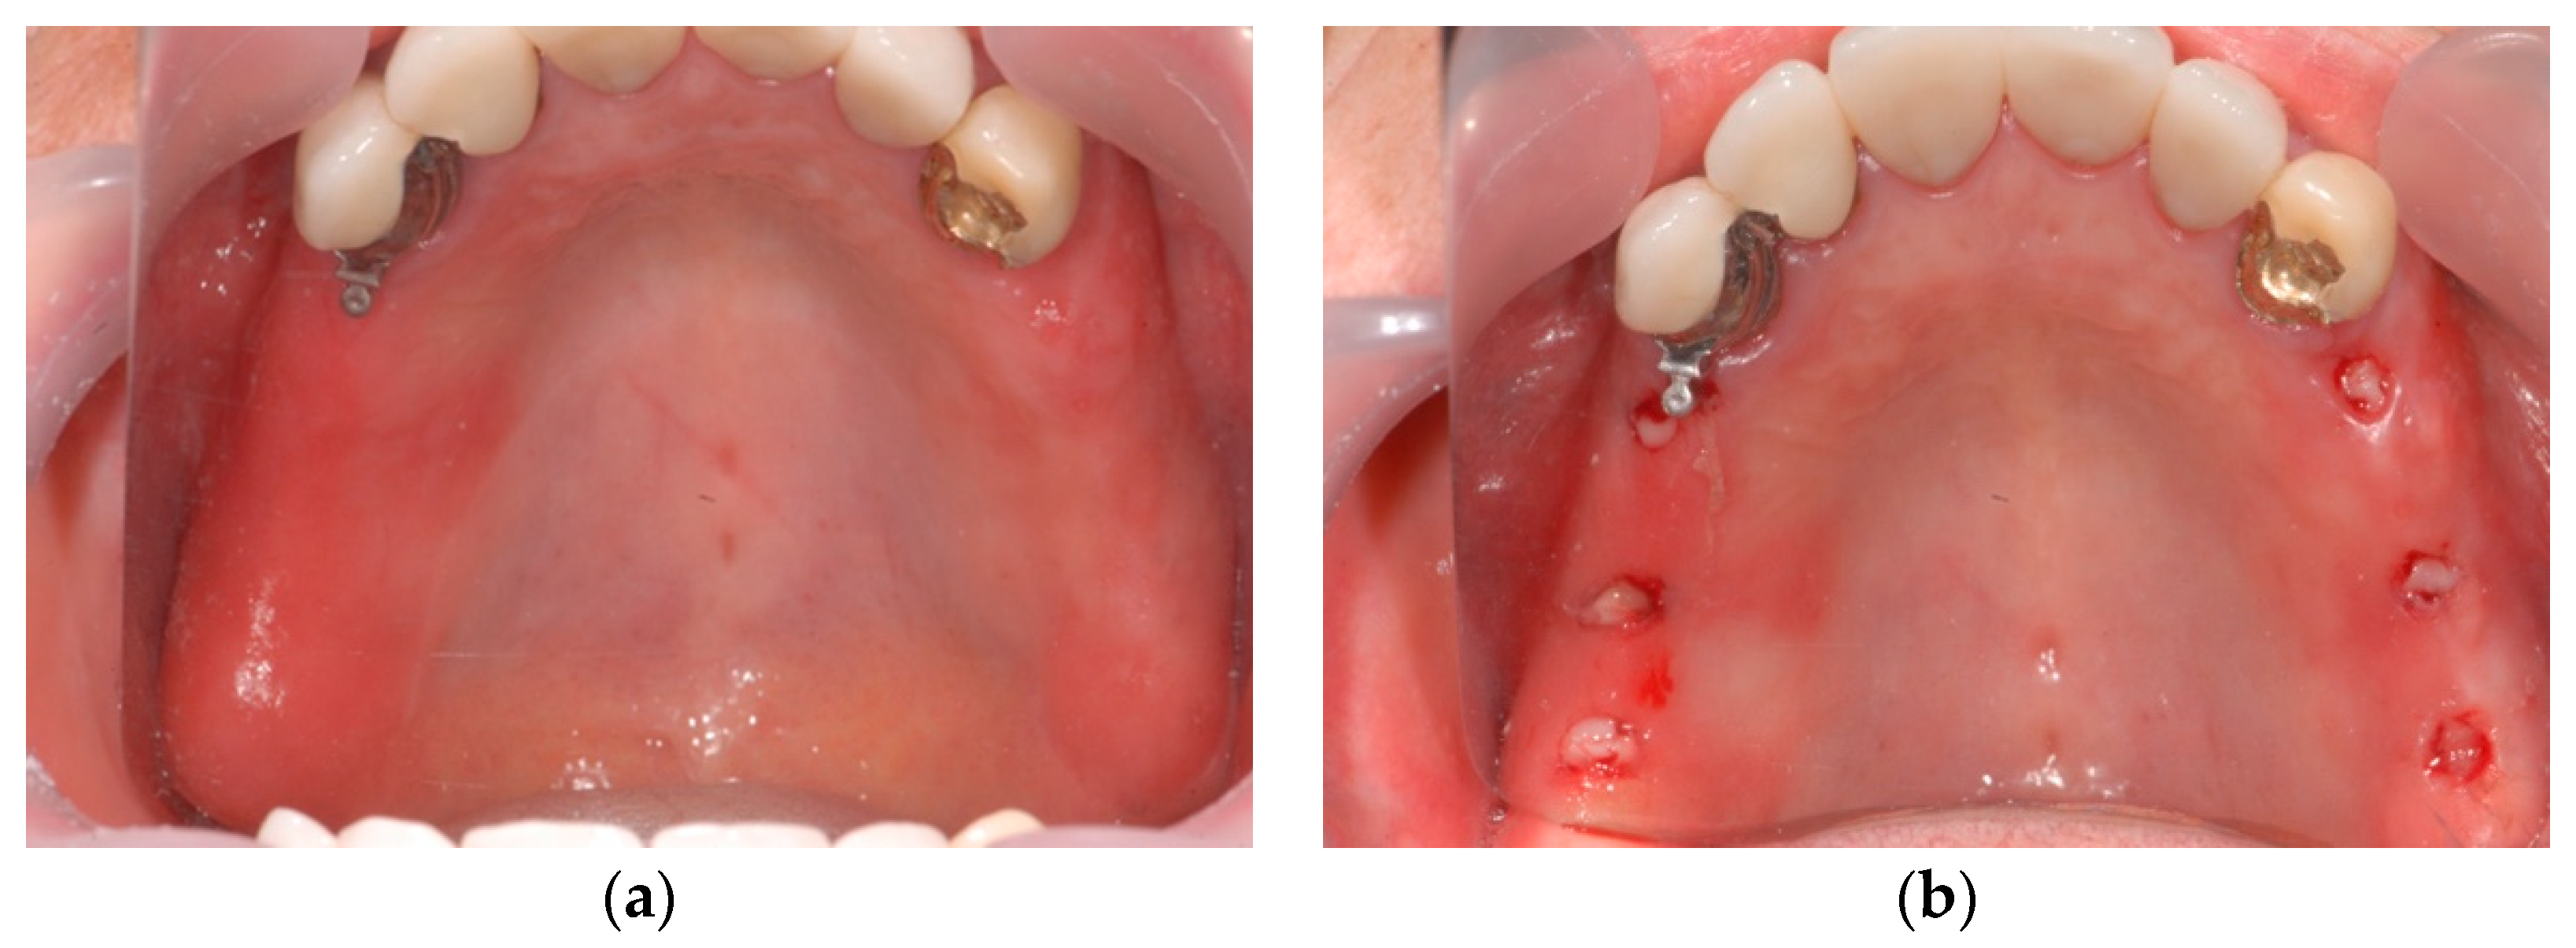

2.6. Case Study